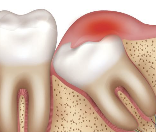

4. 사랑니 염증 – 오른쪽 아래 사랑니 쪽 통증

사랑니가 덧니로 나거나 발치 후 염증이 생기면,

침을 삼킬 때 턱 아래부터 오른쪽 목으로 통증이 퍼질 수 있어요.

- 사랑니 주변 잇몸이 붓고 통증

- 오른쪽으로 음식 씹기 힘듦

- 귀 밑과 목 옆 통증 함께 나타남

- 구강 열감 또는 구취 동반 가능

사랑니 염증은 편도선, 턱관절, 림프절까지 함께 자극하므로 종합적인 진단이 필요해요.